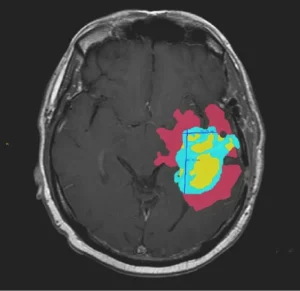

For surgical planning AI, accurate segmentation not a luxury; it is the fundamental prerequisite. If an AI is tasked with delineating a tumor for resection, a 2 mm error in boundary definition could lead to incomplete resection (endangering the patient) or excessive tissue loss (resulting in functional deficit).

Ans: Inaccurate segmentation creates “geometric noise.” A 1 mm deviation in 2D contouring can result in a 3–5% volumetric error in 3D models. For orthopedic or cranial guides, this leads to poor mechanical fit, potentially causing intra-operative misalignment or hardware failure.

Ans: Fully automated models often fail at “edge cases” like post-traumatic anatomy or rare pathologies. HITL ensures clinical experts validate every boundary, delivering accurate “ground truth” for high-risk operating room environments.